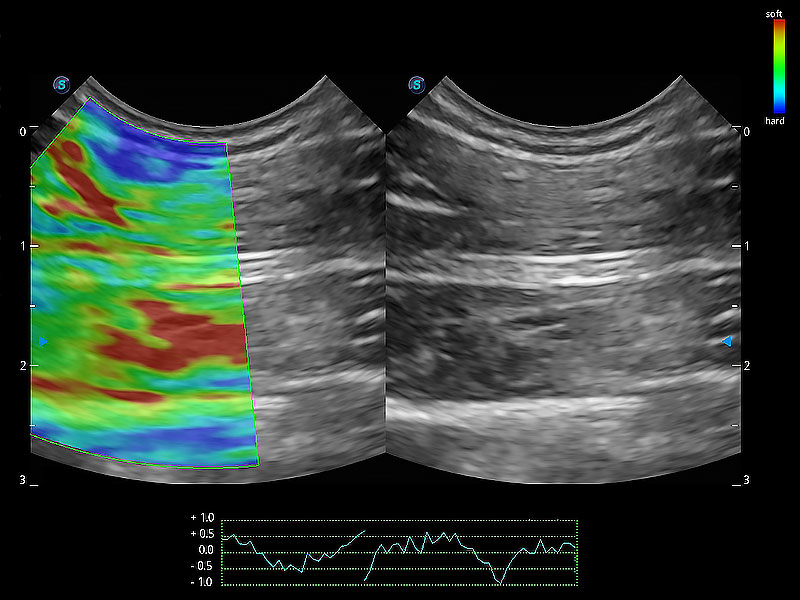

• 应变式弹性成像

操作简便,无需高频度外力作用即可真实反映组织的形变,快速评估肿瘤良恶性。